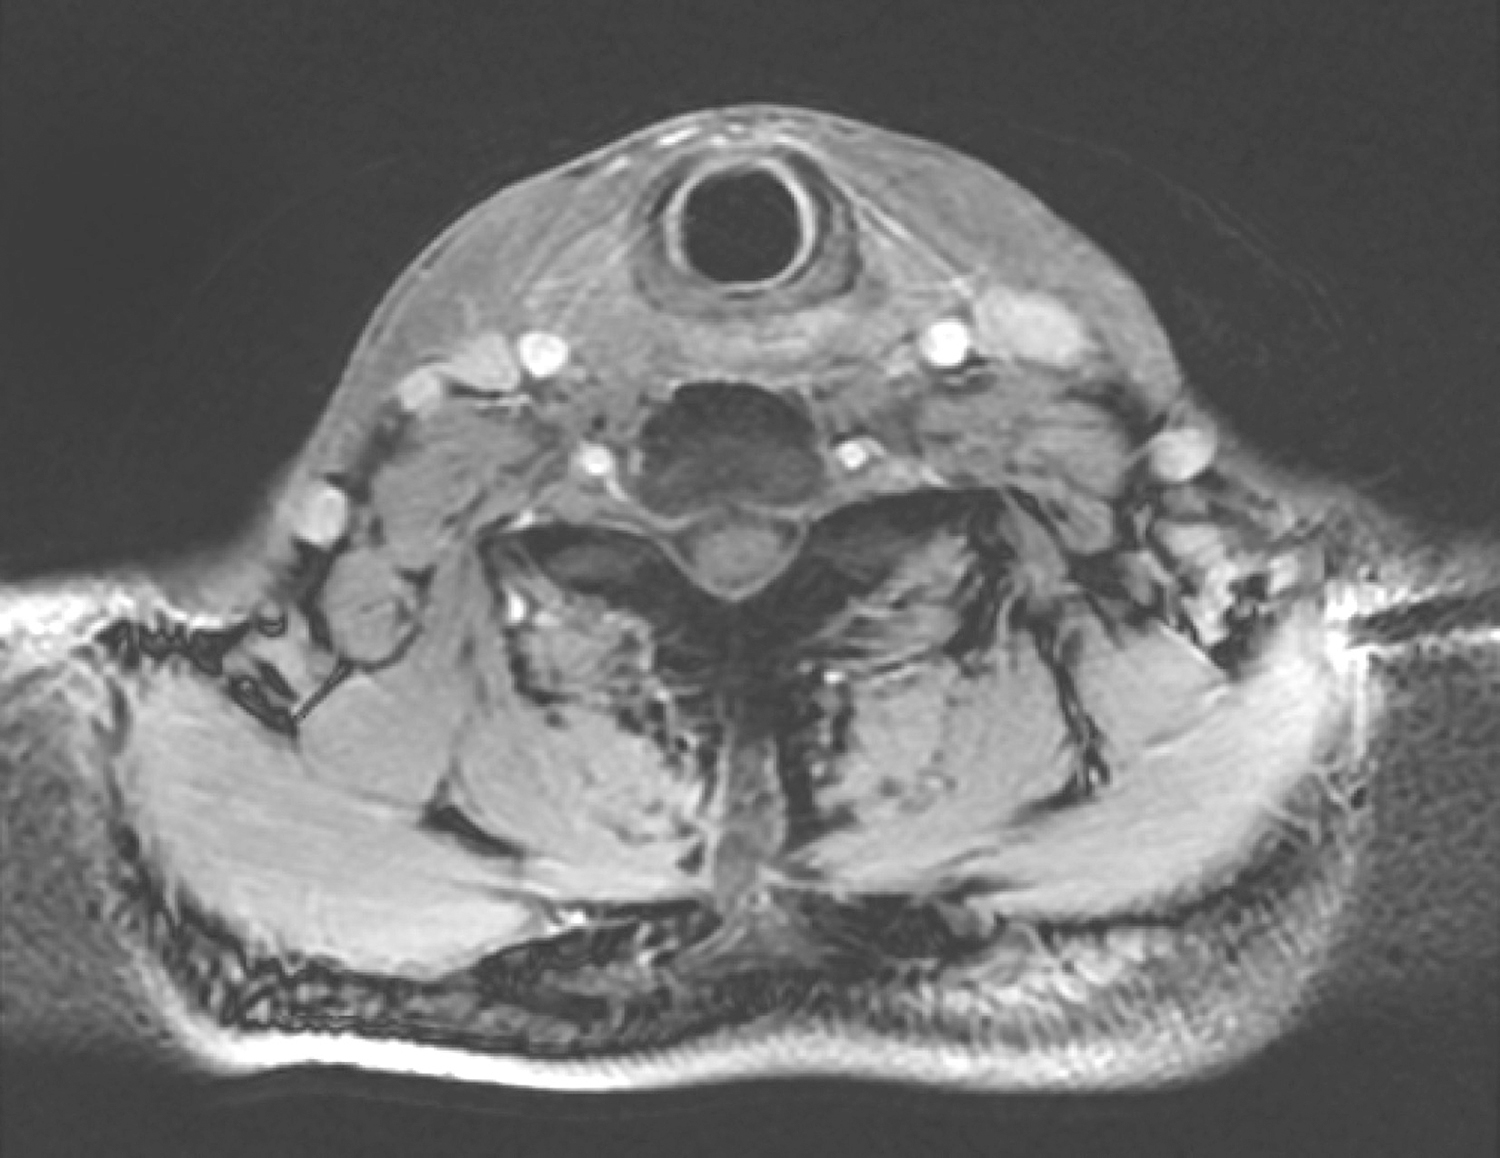

18.2016年1月26日下咽MRI

“右梨状窝癌放化疗后1年余”复查,参阅2014年10月27日下咽部MR图像

右侧梨状窝内侧壁偏上方可见结节状异常信号,最大横断面约为1.5cm×1.8cm,T2/FS呈稍高信号,增强扫描呈中等度强化,贴邻右侧杓状会厌襞,双侧杓状会厌襞黏膜较前增厚(图18),以上请结合镜检。甲状软骨右旁软组织影较左侧饱满,请结合临床。双侧颈深组可见多发小淋巴结,大者短径约0.5cm,同前相仿,请随诊。

图18 右侧梨状窝内侧壁偏上方可见结节状异常信号